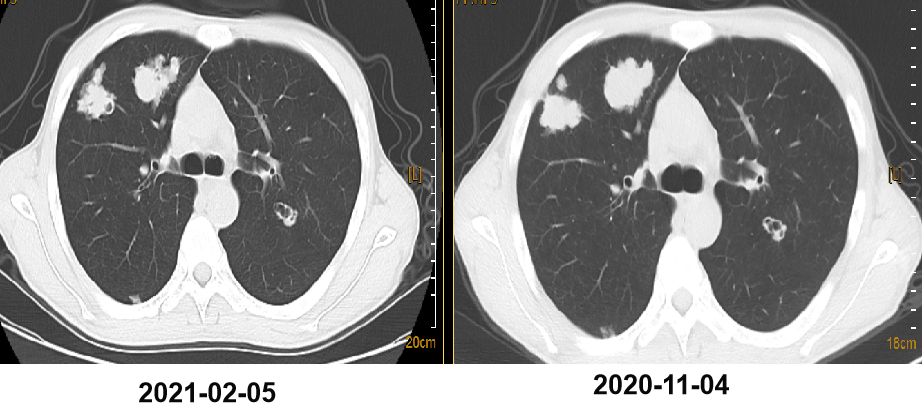

二 病例分享 专家简介 01 基本情况 刘某某,男性,28岁。 主诉:大便次数增多2月。 首诊时间:2018-07-03,北京大学人民医院。 既往史:右踝关节骨折术;痔疮病史。 个人史:无特殊。 家族史:其父为小细胞肺癌患者。 入院查体:ECOG 1分,无明显阳性体征。 02 初诊病史 肿瘤标志物:CEA 19.45 ng/ml。 肠镜及病理:直肠(距肛门约8cm处),直肠腺癌。 胸腹盆增强CT:1.双肺多发结节,考虑转移瘤可能性大;2.肝S6段异常密度灶;3.下段直肠癌可能性大。 盆腔增强MRI:(中位)直肠癌、T(3b)、N(2b)、癌结节(0)、CRM(阳性)、EMVI(阴性)、非区域淋巴结(阴性)。 上腹部增强MRI:肝S6段小结节,不典型血管瘤可能大。 初步诊断: 1.直肠癌(cT3N2bM1aIVA期 )肺转移; 2.痔疮; 3.右踝关节骨折术后; 4.肝血管瘤。 03 治疗方案 外院:XELOX。 我院首诊:2018-07-18。 免疫组化:MLH1(+),PMS2(+),MSH2(+),MSH6(+)。 2018-07-25至2018-09-26 XELOX *2+局部放疗*25f,PD。 基因检测(2018-10-23):KRAS、NRAS、BRAF基因均未见突变。 二线治疗:2018-10-18至2019-03-01 贝伐珠单抗+FOLFIRI*9 (SD→PD)。 疗效评估 三线治疗:2019-03-28至2019-07-23 西妥昔单抗+伊立替康+雷替曲塞*6(SD→PD)。 疗效评估 2019-07-25 瑞戈非尼 80mg po。 2019-09-26 复查:SD,瑞戈非尼 120mg po。 2019-11-21 复查:PD,瑞戈非尼 160mg po。 疗效评估 2019-12-19 至2020-09-24 信迪利单抗 200mg q3w +瑞戈非尼80mg po d1-d21 q4w。 2020年 ASCO 更新的瑞戈非尼+纳武利尤单抗(regorafenib+nivolumab)在晚期结直肠癌或胃癌患者中的Ib期临床试验(REGONIVO, EPOC1603)。 疗效评估 2020-09-26 盆腔增强MRI:直肠癌治疗后复查,与2020-05-10 MRI比较:直肠壁增厚程度较前似进展;直肠下段偏左侧新发不规则异常信号,考虑瘘管/脓肿形成。 考虑直肠下段脓肿,行抗感染治疗。 并于 2020-10-14 在气管插管全身麻醉下行腹腔镜下乙状结肠造口术。 2020-11-06 至2021-02-05 信迪利单抗200mg q3w+呋喹替尼3mg d1-21 q4w。 双肺多发转移瘤,对比 2020-11-04 CT较前增大、部分空洞形成。 TAS-102:新型口服细胞毒性药物 2021-V1版NCCN指南和2021 CSCO指南推荐更新:TAS-102±贝伐珠单抗(Bev)作为mCRC三线标准治疗。 2021-02-05 至今 TAS-102 60mg bid d1-5,d8-12,q4w 联合信迪利单抗200mg q3w。 不良反应 西妥昔单抗:皮疹; 瑞戈非尼:手足综合征; PD-1抑制剂:免疫性甲状腺炎; TAS-102:骨髓抑制(中性粒细胞IV度下降、贫血)。 04 诊疗小结